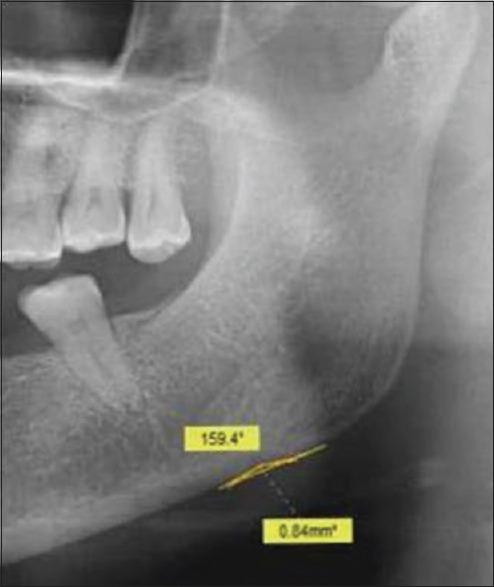

Osteoporosis is a specific condition which is characterized by low bone mineral density (BMD) and deterioration of bone structure resulting in an increased susceptibility to fractures. It contributes to a great deal of morbidity and mortality, and is a large burden to the healthcare system, especially in the case of the elderly population. In the last four decades, a plethora of studies have reported characteristic oral radiographic findings in the early stages of osteoporosis, suggesting the possible use of oral radiographic signs for the early detection of the condition. Digital orthopantomographs (OPGs) are usually taken for the screening of dental patients during routine dental evaluations. These radiographs and the characteristic changes seen on them may have a significant role in the screening for initial osteoporotic changes. A number of precise radiomorphometric indices of the mandible have also been developed to allow quantification of the mandibular bone mass for identification of the initial signs of osteoporosis. The present review focuses on the possible role of panoramic radiographs in the initial screening for osteoporosis in dental clinics in high-risk groups.

骨质疏松症是一种特殊的病症,其特征是骨矿物质密度(BMD)低且骨结构恶化,导致骨折易感性增加。它导致大量的发病和死亡,给医疗保健系统带来巨大负担,尤其是在老年人群中。在过去的四十年里,大量研究报告了骨质疏松症早期阶段典型的口腔放射学表现,这表明口腔放射学征象可能用于该病症的早期检测。在常规牙科评估期间,通常会拍摄数字化曲面断层片(OPG)以筛查牙科患者。这些X光片及其上所见的特征性变化可能在初步骨质疏松症变化的筛查中发挥重要作用。还开发了一些精确的下颌骨放射形态计量学指标,以便对下颌骨质量进行量化,从而识别骨质疏松症的初始迹象。本综述重点关注全景X光片在高危人群牙科诊所骨质疏松症初步筛查中的可能作用。